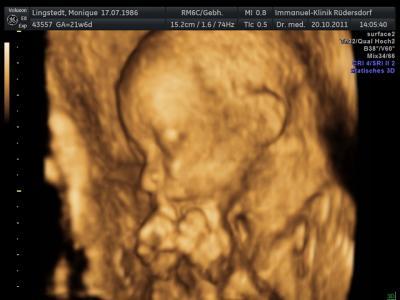

soo war heute um 13 uhr bei der fd..und es ist alles wunderbar..Unser prinz ist ca 472 gramm schwer und ca 25 cm klein:D wird nen schlanker wie sein papa:D sonst ist auch alles i.o. händchen füsschen kopf alles drann wos sein soll:)...und der papa is stolz wie oskar..er war das erste mal dabei:) so noch ein 3d bildchen von unsrem geliebten baby

Bild zu FD - Forum für Februar - Mamis